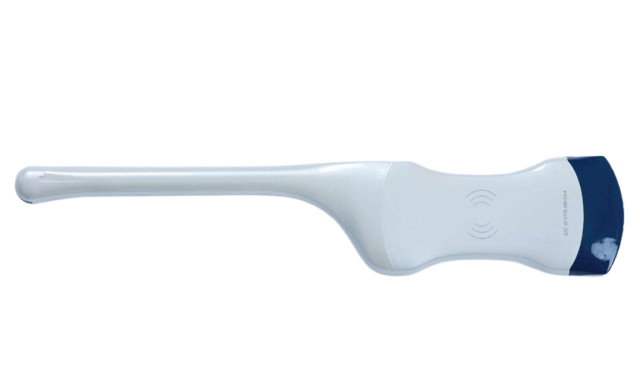

SonoSmart 2 in 1 Convex-TVS Wireless Ultrasound Probe

The 2 in 1 Convex-TVS Wireless Ultrasound Probe by SonoSmart is a modern portable ultrasound scanner designed for fast, accurate, and reliable diagnosis. This wireless USG probe in Bangladesh combines Convex and Transvaginal (TVS) scanning in one compact device. It connects wirelessly to smartphones, tablets, and computers, making it ideal for hospitals, clinics, diagnostic centers, and mobile medical services.

- Product Name: Convex-TVS Wireless Ultrasound Probe

- 2 in 1 Probe: Convex/TVS/Phased Arry

- Brand : SonoSmart

The 2 in 1 Convex-TVS Wireless Ultrasound Probe from SonoSmart is an advanced medical imaging solution for professionals who need speed, accuracy, and mobility. This wireless ultrasound probe in Bangladesh is specially designed for gynecology, obstetrics, abdominal, and general diagnostic imaging.

Unlike traditional ultrasound machines, this handheld ultrasound scanner works wirelessly, eliminating cables and bulky equipment. Doctors can perform examinations directly from a smartphone or tablet, making it one of the best portable ultrasound scanners in BD.

Wireless & Portable Design

The SonoSmart Wireless USG Probe uses high-speed Wi-Fi connectivity to transmit images in real time. Its compact and lightweight design makes it perfect for emergency rooms, ICU, outdoor medical camps, and home healthcare services.

Portable & handheld design